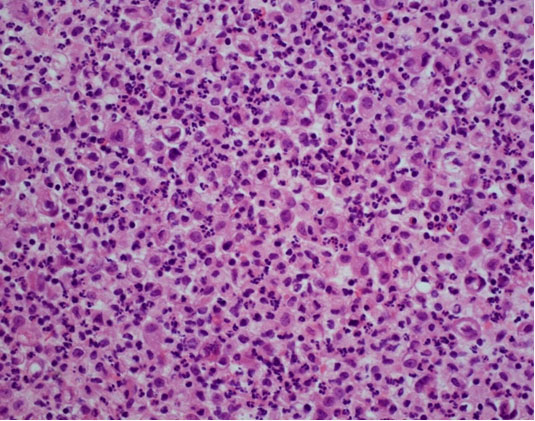

The patient was admitted to the hepatology inpatient service with consults from rheumatology, infectious disease, hematology, nephrology, pulmonology, and interventional radiology for a multidisciplinary approach to management. He underwent paracentesis followed by thoracentesis and an ultrasound guided peritoneal nodule biopsy. Turbid white chylous fluid (1200 mL) was removed from the left chest. The initial clinical impression from pulmonary was that the bilateral chylous effusion was likely secondary to superior vena cava syndrome and left brachiocephalic obstruction caused by lymphadenopathy. He was commenced on a low cholesterol diet and nutrition was consulted. Laboratory results from the first peritoneal tap showed atypical mesothelial cells indeterminate for malignancy (Figure 2). Subsequent thoracentesis (Figure 3) and paracentesis (Figure 4) specimens had higher cellular yield and revealed highly atypical mesothelial cells with high nuclear to cytoplasmic ratios and prominent nucleoli suggestive of malignant mesothelioma. Tumor cells were immunoreactive with Calretinin immunohistochemistry stain (Figure 5) which supported mesothelial origin rather than an epithelial origin (carcinoma). The diagnosis was further confirmed by an ultrasound guided peritoneal nodule biopsy which showed a consolidation of epithelioid tumor cells consistent with malignant mesothelioma, epithelioid type (Figure 6). Immunohistochemical staining of the omental biopsy for Ki 67 staining showed a high proliferative index > 10% (Figure 7). The tumor also contained foci of inflammatory cells including many plasma cells. These inflammatory cells could be reactive to the tumor or related to an underlying autoimmune or inflammatory process.

Figure 4: Malignant mesothelioma with marked acute and chronic inflammation, Peritoneal fluid (Cell block, low power, H&E stain).

Figure 6: Omental core biopsy, malignant mesothelioma, epithelioid type, H& E stain, high power.